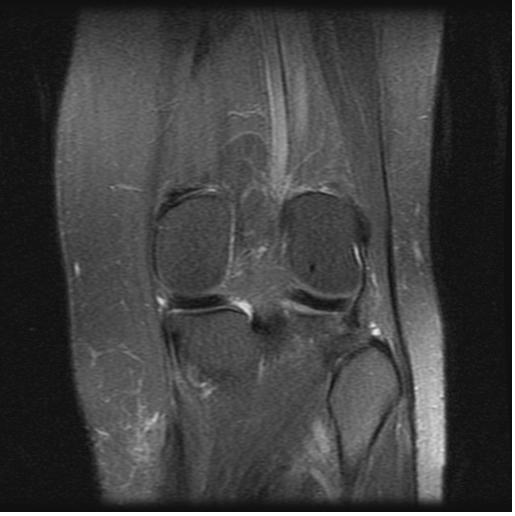

Click on images to enlarge.

My computer tech (who also has a certification in x-ray/mri technology) helped me to upload these two MRI images. He said he could also see what Dr. Main was talking about in that the white markings showing up on a T2 image is fluid accumulation above/around the head of the fibula. My only other diagnostic tool was a repeated Thermography scan on 5-7-13 that reiterated that my hyperthermia at the left popliteal fossa remained and was unchanged from previous scan on 12-6-11 and findings were consistent with underlying joint dysfunction.

Quoting from my office chart note the pertinent findings with the bold type my emphasis: “Musculoskeletal examination demonstrates her to walk about the clinic with assistive devices. She has a Coban wrap involving her left lower extremity from the knee to the ankle. Once removed she does have mild swelling overlying the lateral aspect of the left proximal leg region just below the level of the lateral joint line. There is a trace amount of swelling involving the left ankle….She is tender to palpation overlying the anterior tib/fib ligament, the distal tib/fib syndesmosis, the ATFL and the CCFL….Dorsiflexion and external rotation stress test elicits minimal pain at the ankle but more pain along the mid syndesmotic region. Cotton squeeze test is negative distally but is positive proximally….Examination of the left proximal tib/fib articulation demonstrates evidence of marked increase mobility of the proximal fibula in relationship to the tibia. She is noted to have a posterior and inferior instability pattern. This instability becomes worse with the leg externally rotated and it tightens with the leg internally rotated….X-rays from an outside facility reviewed about the left knee including AP and lateral demonstrates no gross evidence of arthritis changes present. The overall articulation of the proximal tib/fib joint appears to be well aligned….X-rays obtained today of her left ankle in our facility, AP, mortis and lateral views demonstrates the syndesmosis and ankle mortis to be well aligned. There are no signs of fractures or avulsion injuries noted….Outside MRI of left knee is also reviewed, which demonstrates no gross evidence of collateral or cruciate liagment tear or laxity or involvement. The meniscus appears to be intact. Minimal arthritic changes are present. There is mild increased fluid accumulation and swelling around the proximal tib/fib articulation.”